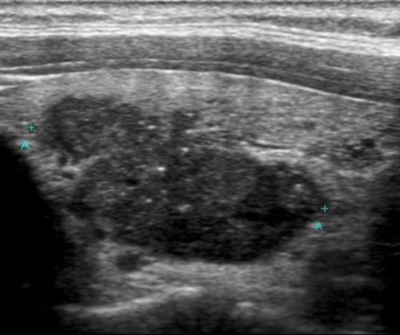

Bu tipteki kanserler genellikle 20-50 yaş arasında, kadınlarda erkeklere göre 3 kat daha fazla görülür. 14 yaşından küçük çocuklarda da görülen en sık tiroid kanseri bu tiptedir. Tiroid kanserlerinin % 90 ı bu tiptir. Genellikle uzun yıllar (bazen 30 yıl) hiç büyümeden 1 cm nin altında kalarak belirti vermeyebilirler ve başka bir sebeple örneğin guatr veya hipertiroidi nedeniyle bezin ameliyatla çıkartıldığında tesadüfen bulunurlar. Son yıllarda check up programları sırasında hassas ultrasonografi aletleri ile tetkik sırasında sıkça bulunmaya başlamışlardır. Bu tipteki kanserler Türkiye’de bizim yaptığımız bir çalışmada genel nüfusun % 2 sinde mevcuttur ve kişiler hasta olduklarını bilmemektedirler. Bazı ülkelerde bu oran halkın % 30 u kadar yüksek oranlara çıkar (Japonya, Finlandiya). Bu durum yüksek miktarda deniz ürünü yenmesi ve bununla alınan aşırı miktarda iyotun tiroid bezinde iltihaplanmaya ve bu iltihap zemininde kanser çıkmasına bağlanmaktadır.

Papiller kanserin tedavisi cerrahidir ve total tiroidektomi ile tedavi edilmelidir. Hastalara ameliyat sonrası 10 mm den küçük bir “mikrokanser” varlığında tiroid hormonu verilmesinden başka bir tedavi uygulanmaması genel bir kabul görmüş yöntemdir. Ancak kanserin lenf bezlerine atlamış olması, kanserin tiroid çevreleyen kapsüle gelmiş olması ve kanser çapının 10 mm den büyük olduğu hallerde radyoaktif iyot tedavisi ameliyattan 6 hafta sonra uygulanmalıdır. Bu tedavi hastalığın gerek lokal olarak boyunda gerek uzak metastaz şeklinde geri gelmesi olasılığını azaltır. Hastaların boyunda lenf bezi tutulumu olduğu taktirde tiroid ile birlikte lenf bezlerinin de bir blok halinde çıkartılması gerekir. Bu durumdan ameliyat öncesi şüphelenildiğinde bu lenf düğümü tiroid ameliyatından önce hiçbir şekilde cerrahi olarak çıkartılmamalı, gerekiyorsa iğne biyopsisi ile tanı konmalı ve doku bütünlülüğü bozulmadan hastanın tiroid bezi lenf bezleri ile birlikte çıkartılmalıdır. Bu ameliyata total tiroidektomi+modifiye radikal veya fonksiyonel boyun lenf disseksiyonu ameliyatı adı verilir.